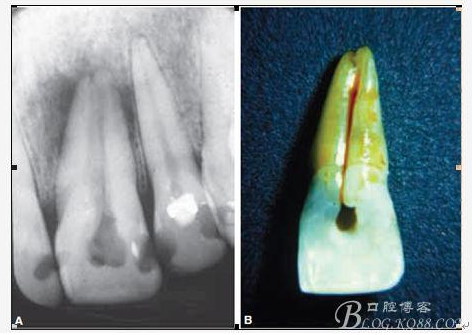

D、牙根的內外吸收 這個目前具體機制也不是非常明確,只要能想到這個層面,通過X片檢查不難發(fā)現,尤其到了有臨床癥狀的時候;

E、牙齒本身的畸形與缺陷 常見的比如下5的畸形中央尖以及切牙的舌側窩、深及根尖區(qū)的舌側溝或者牙中牙等等;